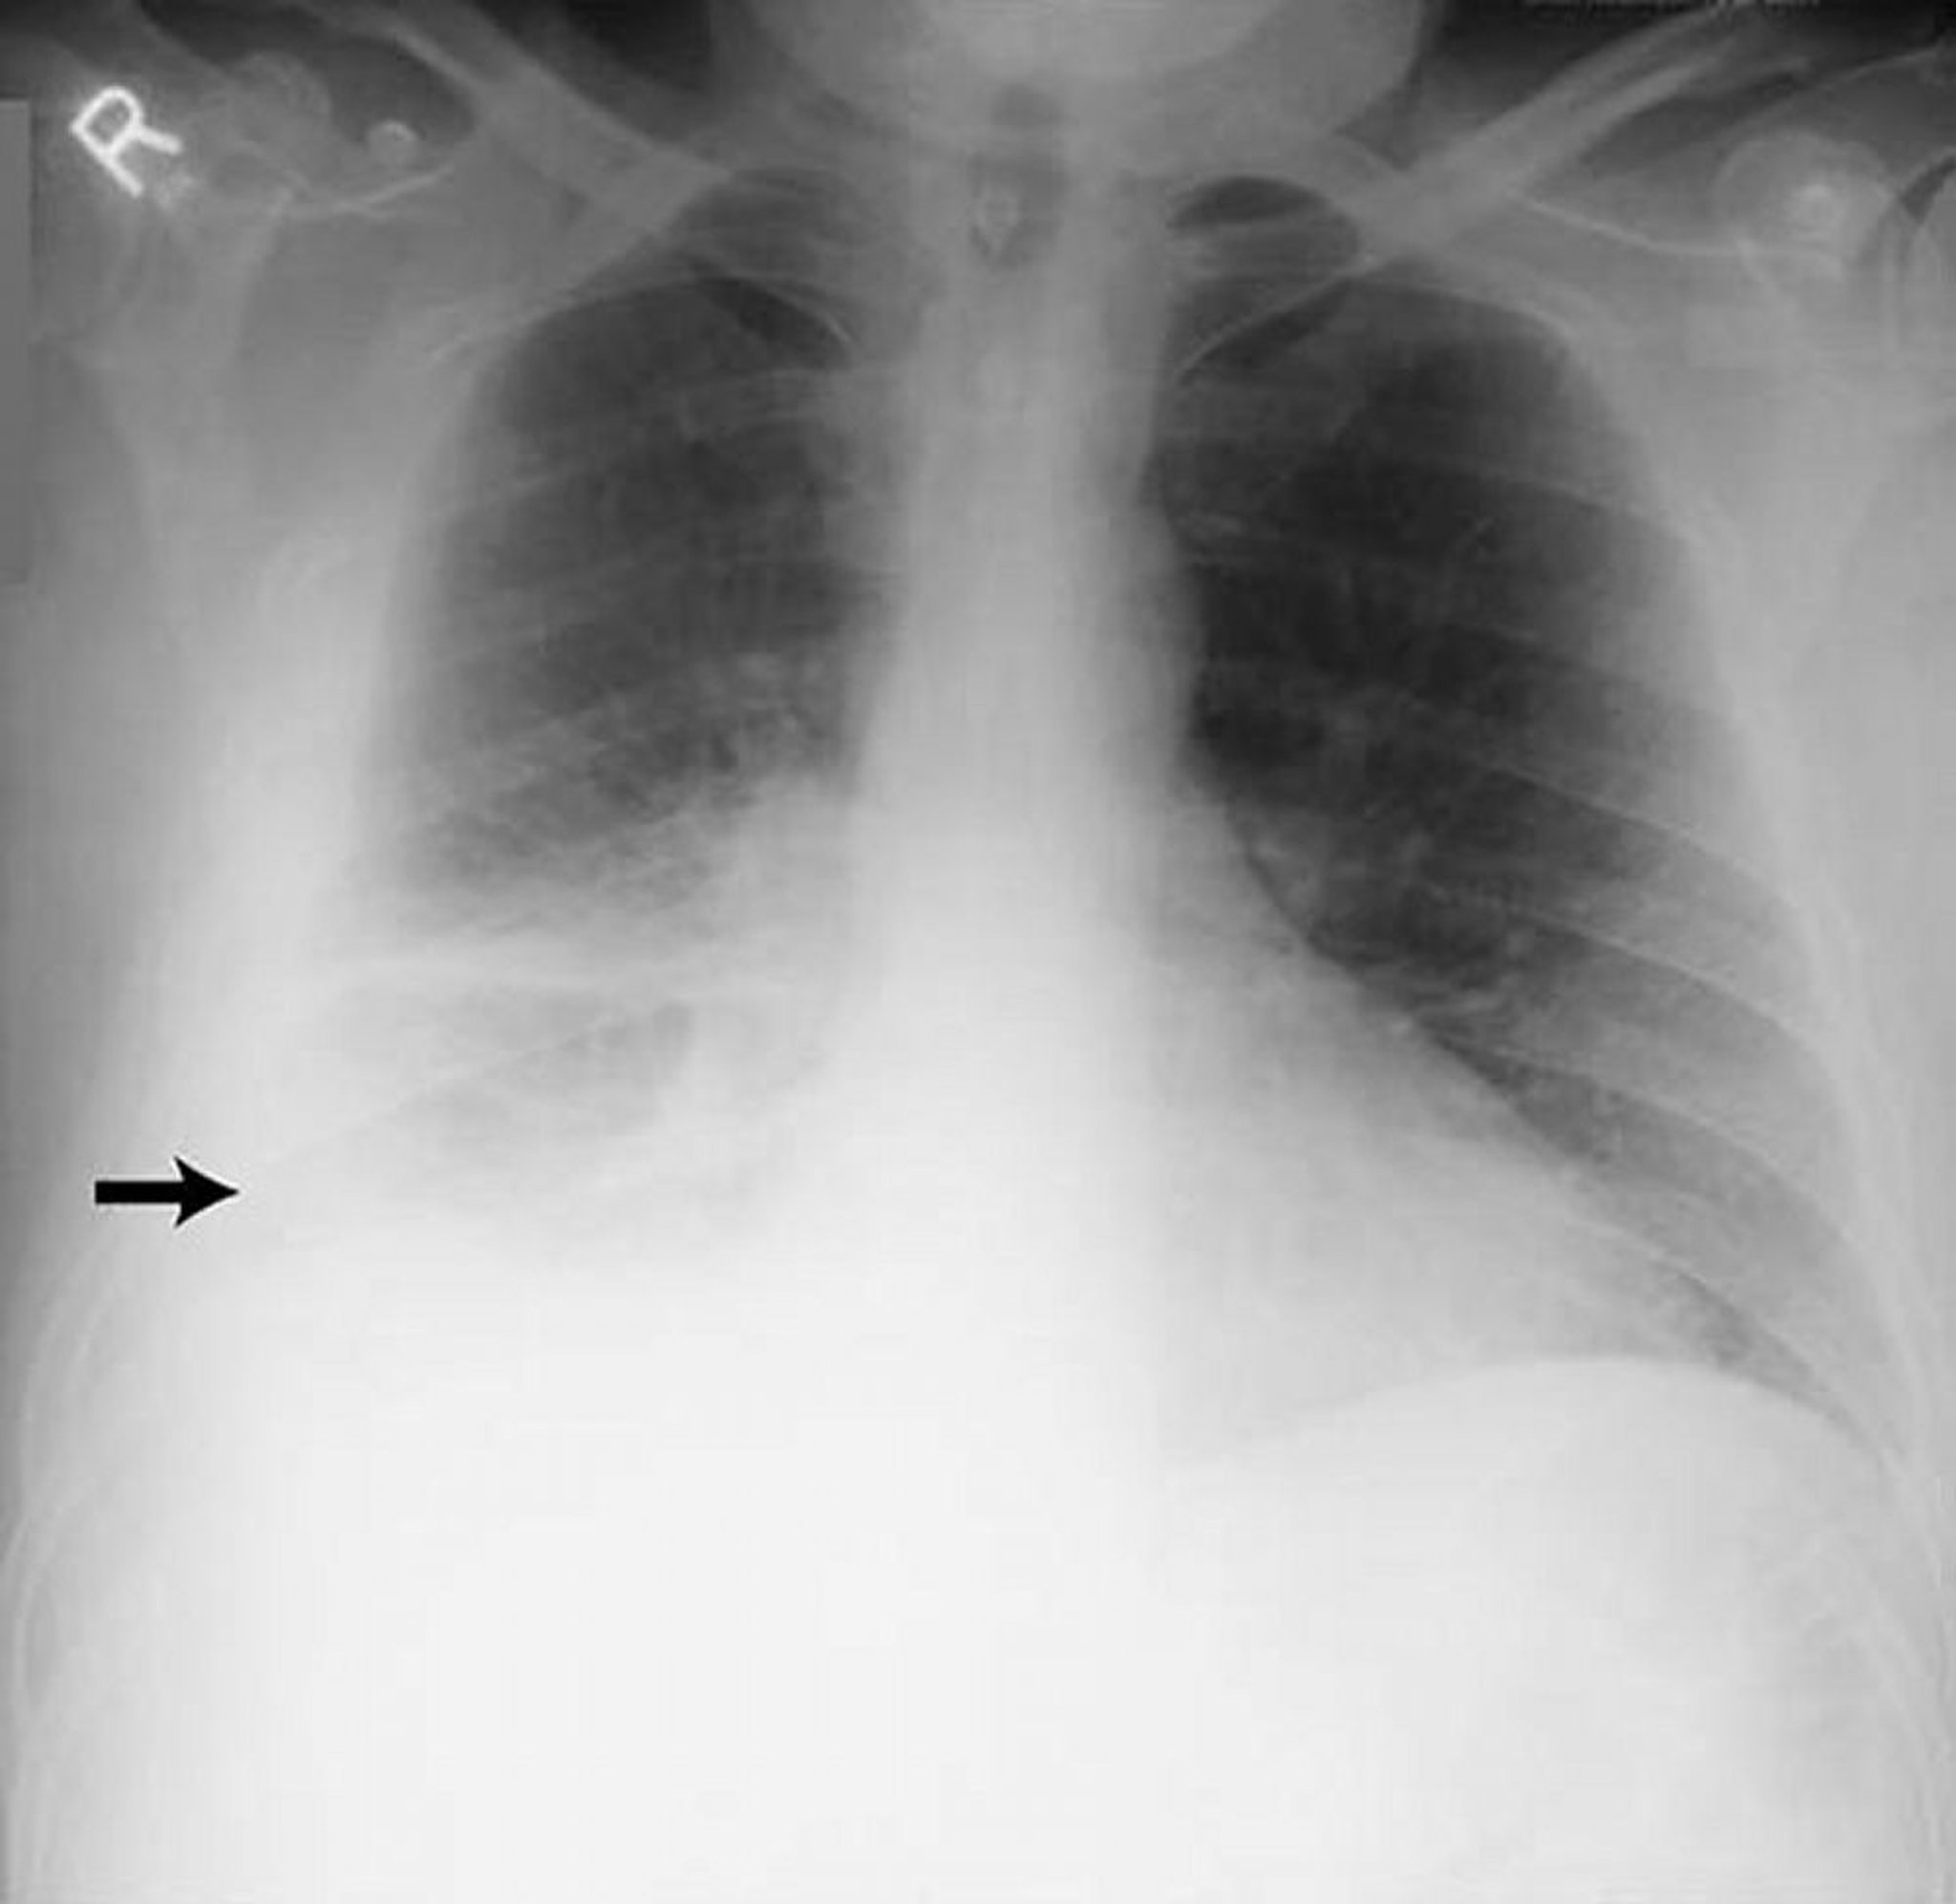

Pleuraerguss - groß

Großer rechtsseitiger Pleuraerguss (Pfeil) bei einem Patienten mit rheumatoider Pleuritis.

By permission of the publisher. From Huggins J, Sahn S. In Bone's Atlas of Pulmonary and Critical Care Medicine. Edited by J Crapo. Philadelphia, Current Medicine, 2005.